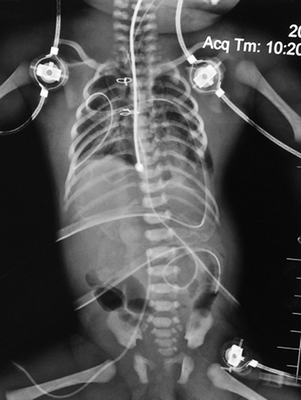

На рентгенограмме органов грудной клетки отмечалось сужение средостения, образованное сосудистым пучком. Легочные поля не изменены. При риноскопии выявлено значительное искривление носовой перегородки, с фактически полной обтурацией правого носового хода.

При осмотре новорожденной на момент поступления в кардиохирургического отделения перинатального центра ГБОУ ВО СПбГПМУ выявлены все 5 признаков синдрома, в том числе врожденный порок сердца, заболевание классифицировано как 1-й класс по Тояма (рис. 1).

Рис. 1. Новорожденная девочка, 2-х суток жизни, поступившая с диагнозом врожденная эктопия сердца, омфалоцеле

Ребенок был осмотрен коллегией специалистов: неонатологом, кардиологом, кардиохирургом, торакоабдоминальным хирургом, неврологом. Состояние ребенка расценено как стабильное, тяжелое, сознание на момент осмотра медикаментозно угнетено. При поступлении пациентке выполнена обзорная рентгенограмма грудной и брюшной полостей, визуализирующая сердечную тень в проекции эпигастрия, что дало представление о эвентрации сердца на переднюю брюшную стенку, однако не отражало анатомию внутрисердечных структур. Верхняя доля правого легкого ателектазирована, в дистальных отделах обоих легких выявлены признаки интерстициального отека легочной паренхимы. Контуры диафрагмы четкие, ровные (рис. 2). Учитывая отсутствие возможности проведения трансторакального ЭХО-КГ, в силу отсутствия кожно-апоневротического компонента, покрывающего сердце, в рамках предоперационного планирования принято решение о выполнении мультиспиральной компьютерной томографии (МСКТ) области грудной клетки с целью определения анатомии внутрисердечных структур и определения типа врожденного порока сердца.

Рис. 2. Обзорный ренгтеновский снимок, показывающий атипичную локализацию сердечной тени, асимметричное положение диафрагмы, неравномерную пневматизацию легочной ткани

В раннем послеоперационном периоде состояние ребенка тяжелое, относительно стабильное, обусловлено дыхательной недостаточностью, сердечной недостаточностью, в том числе по причине врожденного порока сердца, объемом и травматичностью хирургического вмешательства. По завершении операции выполнена обзорная рентгенограмма грудной и брюшной полостей, на которой тень сердца расположена в левой половине грудной клетки (рис. 10), в верхних сегментах правого легкого сохраняется гиповентиляция, в остальных отделах легких признаки отека, контуры диафрагмы не четкие, в грудной и брюшной полостях определяются дренажи, в просвете трахеи интубационная трубка.

Рис. 10. Обзорный рентгеновский снимок, 1-е сутки после операции, сердце низведено в левую половину грудной клетки, положение диафрагмы асимметричное, пневматизация легких неравномерная